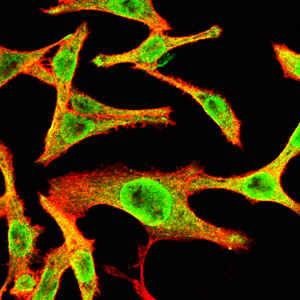

分类: 科研抗体货号: 20334别名: HTK; MYK1; TYRO11应用: IF反应种属: Human